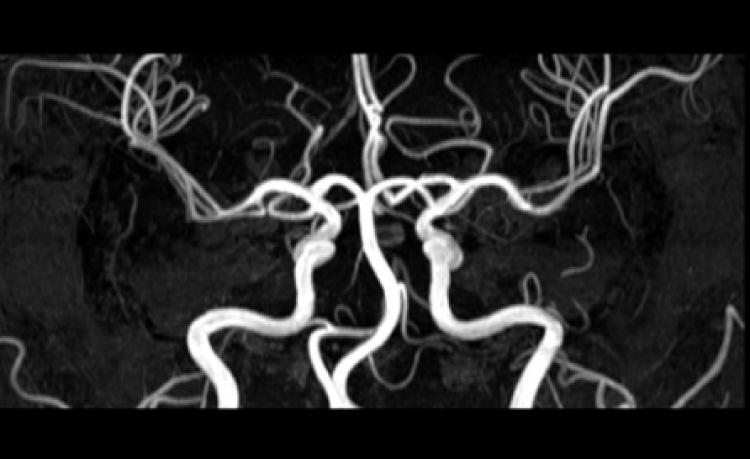

頭頸部血管造影・治療

カテーテルを用いて頭頸部血管造影を行い、脳の動脈、静脈、毛細血管の状態、血管の走行から脳内の病変の診断をする検査です。この検査により脳動脈瘤、脳動静脈奇形(AVM)、脳動脈閉塞及び狭窄などの血管異常の検索と治療を行います。

主な手技

脳血管造影・脳動脈瘤コイル塞栓術・頚動脈ステント治療(CAS)・脳血栓回収術